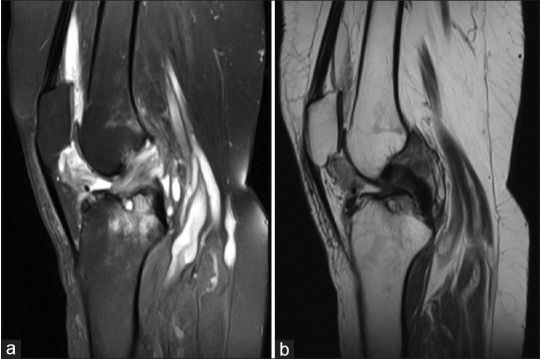

在检查中,患者未借助任何辅助,正常行走且活动自如,没有积液的迹象。既往诊断为骨性关节炎,负重x线显示双侧骨性关节炎严重改变,双侧骨质减少阳性,少量积液,膝内翻畸形。随后,右膝MRI显示前交叉韧带前内侧纤维高信号强度。此外,内侧半月板的后角具有复杂的撕裂和位移,与桶柄撕裂一致。外侧半月板显示信号强度轻微增加,代表内膜变性。MRI还分别显示了侧副韧带和内侧支持带的陈旧损伤和创伤相关发现。此外,还注意到一个小的Baker囊肿(图1)。因此,进行右膝关节镜检查,并进行部分滑膜切除术。关节镜检查后,由于晚期骨关节炎的改变,患者进行了全膝关节置换术。

图1右膝关节磁共振成像的矢状面图; T2视图显示前十字韧带中的高信号强度,Baker囊肿和没有色素沉着绒毛结节性滑膜炎的特征(a和b)。